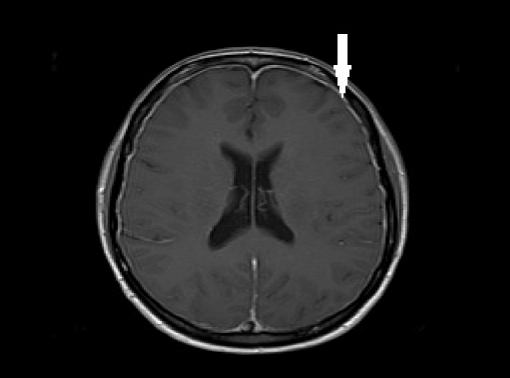

Post-dural-puncture headache (PDPH) is a complication of puncture of the dura mater (one of the membranes that surround the brain and spinal cord). [1] ... Read Article